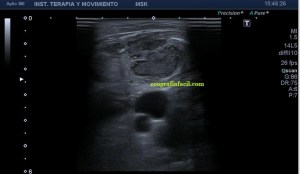

3

El corte en eje largo como te indica el pictograma es muy importante, en teoría debería haber encontrado una estructura redondeada en eje corto y tubular en eje largo, como debiera corresponder a esta lesión vascular, pero los hallazgos no arrojaron dicha imagen.

Demostré el pulso en ambos ejes, pero no pude comprobar la estructura tubular en longitudinal…el motivo, el tamaño de la estructura y su gruesa pared que puedes apreciar en ambos ejes y que correspondía a una incremento de la pared del propio vaso, vaso que se encontraba parcialmente trombosado por este crecimiento de su pared, habitual en estas lesiones post traumáticas, donde el propio vaso sangra y esa sangre se colecciona alrededor el mismo.